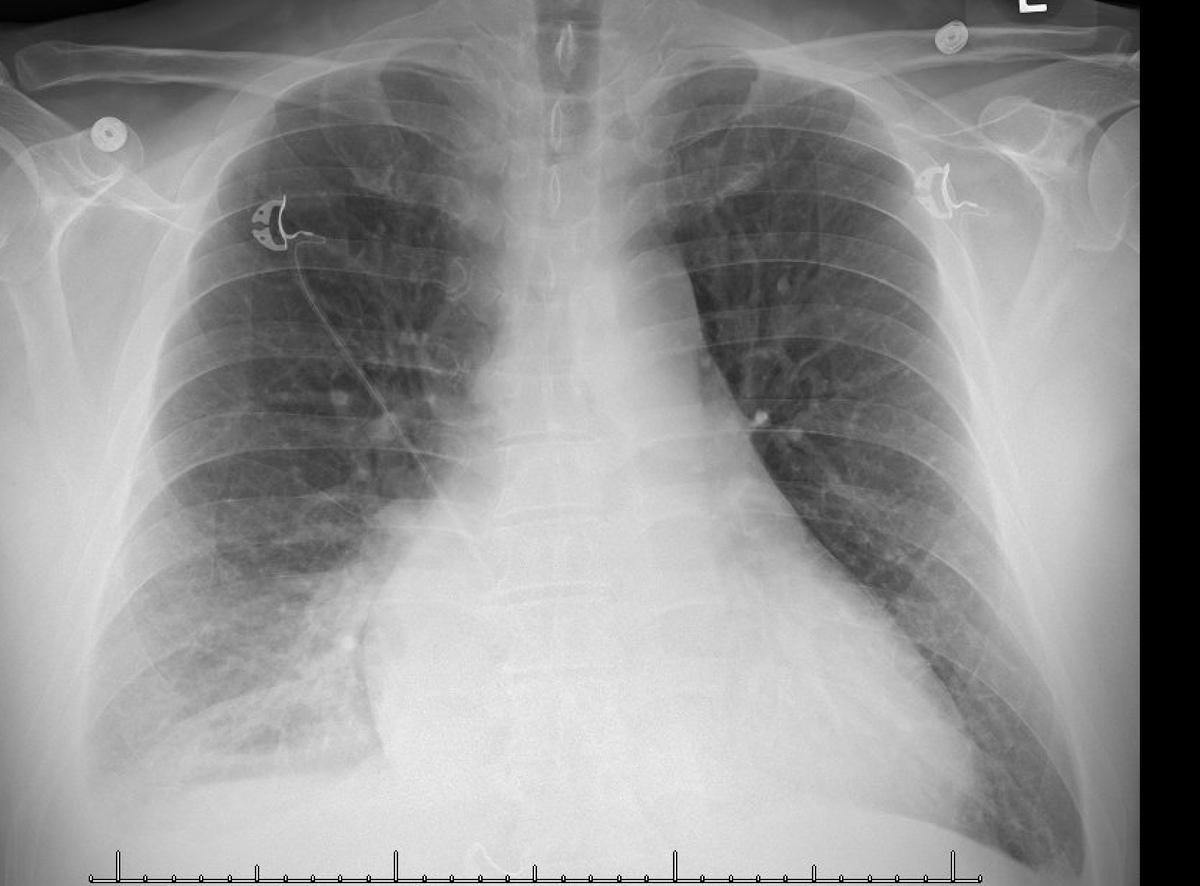

ICU stories: Middle-aged pt w/o significant PMHx presented to the ED on a Friday afternoon w SOB/cough x 2 wks. Vaxed x2 but tested C19(+). BP 120/90, Sat 98% on 2 l/m. ECG: new-onset Afib/HR 140/QTc 500. CXR attached; read as RLL infiltrate. Labs: Na 125, BNP 800 (nl<100),

☝️Full IVC and large R effusion. The admission CXR was read as "no evidence of pleural effusion". This was the chest CT for comparison: